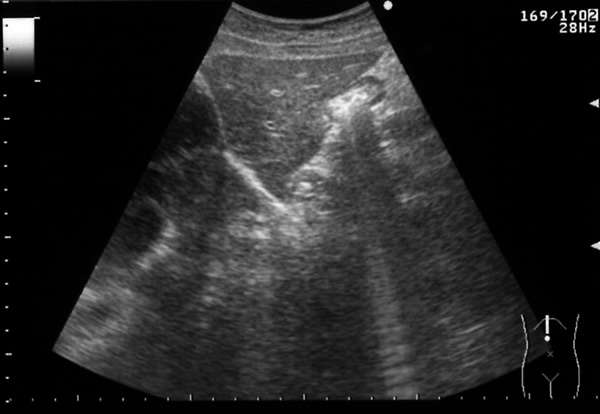

肝臓の正中縦断面のエコー像は、正常肝から、慢性肝炎、肝硬変に従って、断面の辺縁の鋭さが、鈍となり、肝硬変になると表面が凸凹不整となり、内部のきめが粗くなっていきます。

| 正常肝 | 慢性肝炎 | 肝硬変 |